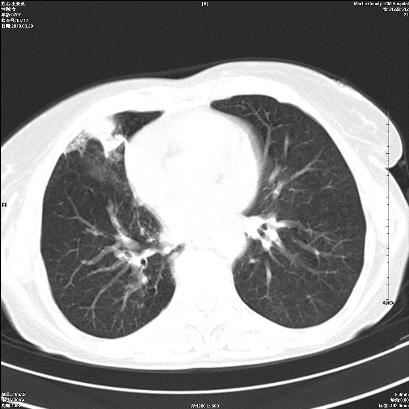

标题: CT25424:女性,70岁,胸闷、咳嗽月余。 [打印本页]

标题: CT25424:女性,70岁,胸闷、咳嗽月余。

右肺上叶支气管开口阻塞,上叶呈不均匀致密影,右肺中下叶内见斑片状密度增高影,上叶见钙化点,纵隔内见钙化淋巴结,桶状胸,右下肺动脉增粗,残根征,意见:1.右肺中心性肺癌;2.右肺陈旧性结核;3.肺心病。

1 右肺门占位伴上叶不张 2 有肺多发感染 3 肝脏转移? 建议增强

考虑右肺中心型肺癌并上叶不张

1、右侧中央型肺癌伴右肺上叶不张建议支气管镜检   2、右肺中叶及下叶陈旧性病灶   3、肝内多发低密度影,肝内多发转移不除外,建议ct增强!

1)考虑右肺中央型肺癌伴右肺上叶肺不张,右肺门淋巴结转移;建议行支纤维镜检查。2)右肺中叶、下叶及左肺上叶舌段感染性病变。3)肝内多发低密度影,不排除转移瘤可能;建议行ct增强扫描检查。

ct所见:右肺上叶肺不张,呈软组织密度影向肺门区聚拢,其内可见含气段支气管及细支气管影,病灶内尚可见钙化结节。右肺上叶支气管狭窄,段支气管壁可见钙化。右肺下叶背段、右肺中叶见不规则小片絮状影及纤维条索影,形态较僵硬。右肺中叶胸膜旁可见多个小结节影。纵膈内见钙化淋巴结。

分析:右侧胸廓及右肺体积缩小,说明病变时间比较长了,应该是有数年的时间了,如果是短期内出现的肺不张,只会引起纵膈向患侧移位,而不会引起胸廓的塌陷。不张的肺组织内可见含气支气管影,说明右肺上叶支气管没有完全中断,只是狭窄。右肺中叶、下叶散在不规则病灶,部分呈纤维化改变。纵膈内的淋巴结大部分钙化。因此,本例给我的感觉良性病变的可能是大。

结论:考虑右肺上叶支气管内膜结核合并右肺上叶肺不张;右肺中叶、下叶陈旧性肺结核改变。